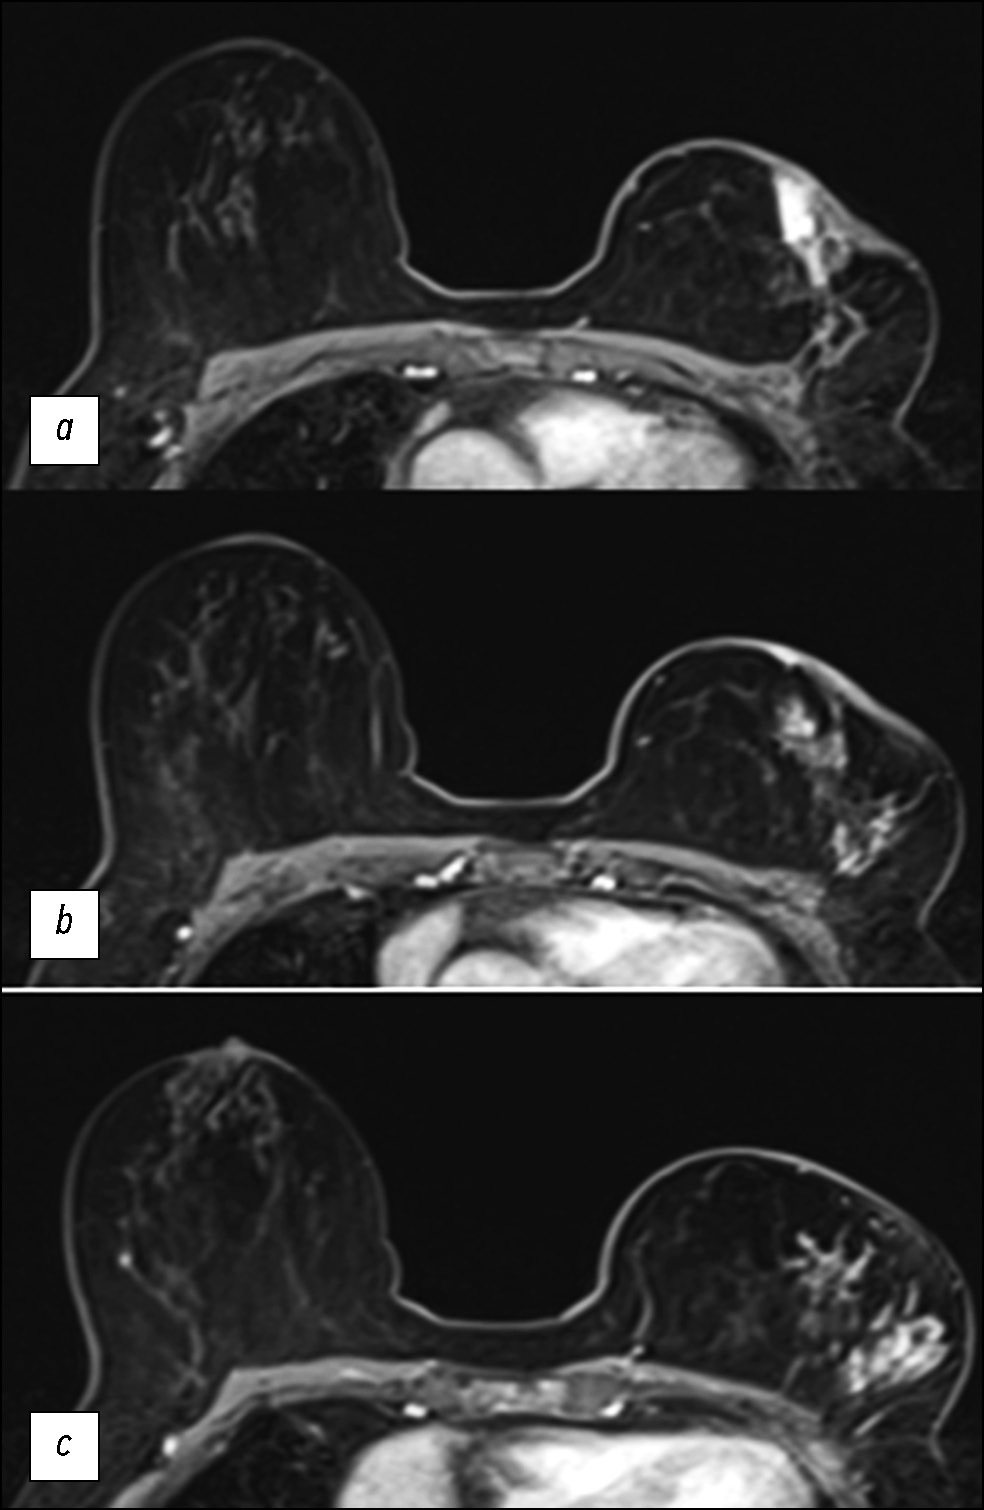

Кроме того, провели МРТ для дополнительной оценки степени распространённости опухолевого процесса и выявления других очагов и получения других значимых сведений. По данным динамических последовательностей МРТ, после введения контраста в наружных квадрантах левой молочной железы наблюдался обширный очаг диаметром приблизительно 7 см с гетерогенным контрастированием и инфильтратами в коже и подкожной ткани, которые были более выраженными в области вокруг ареолы соска (рис. 2).

Рис. 2. Магнитно-резонансная томография. T1-взвешенное трёхмерное изображение в аксиальной плоскости на разных уровнях (a, b, c) в рамках первой динамической системы после введения контраста. Очаг неправильной формы с неоднородным контрастированием левой ретроареолярной области и наружного верхнего квадранта.